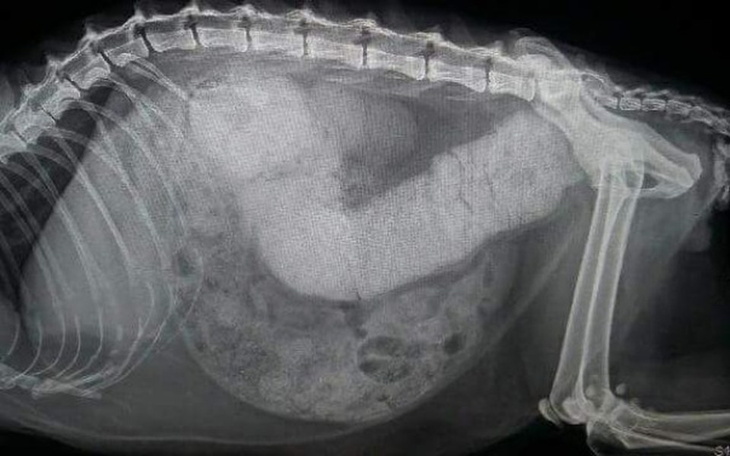

Usg wykazało,że Zosia ma całkowicie zatkane jelita.Nie była w stanie sama oddać kału.

Przeszła zabieg oczyszczenia jelita ( koszt 400 zł ). Niestety nadal jest źle...